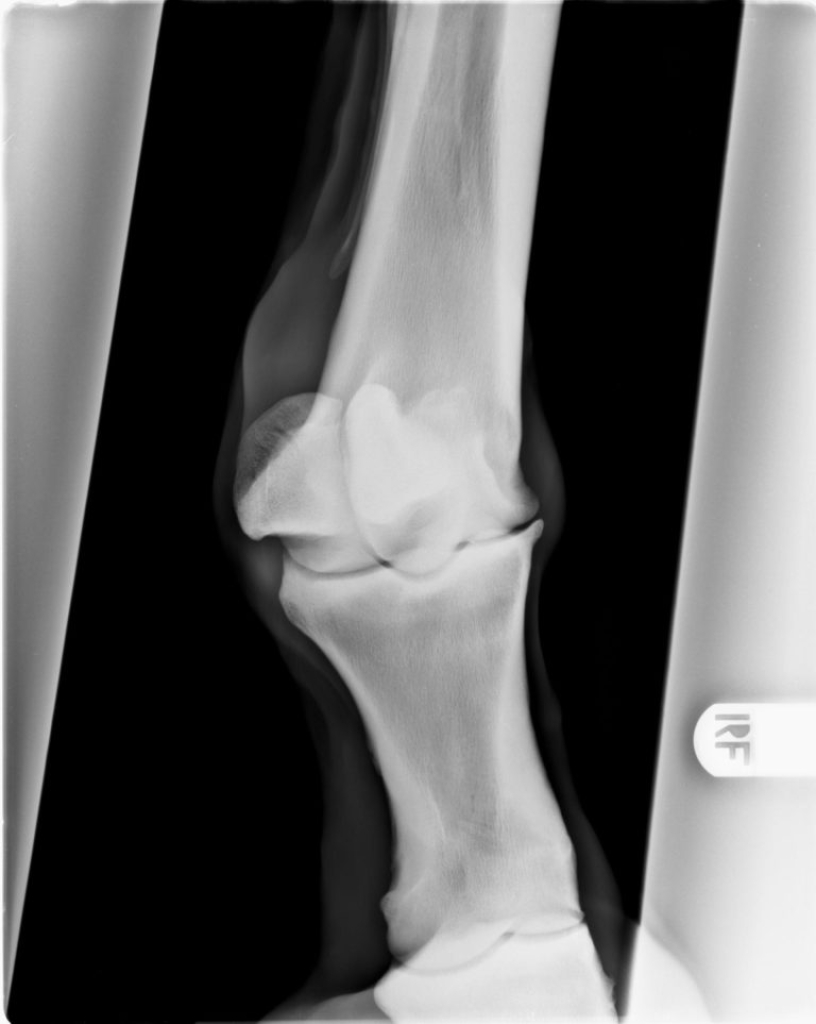

Door een kleine beschadiging kan uiteindelijk soort vicieuze cirkel ontstaan waarbij de kwaliteit van het kraakbeen langzaam aan steeds slechter wordt. Als gevolg van de schade aan het kraakbeen gaat ook het onderliggende bot reageren, het gaat aan de randen van het gewricht nieuw bot vormen. Dit is op een röntgenfoto goed zichtbaar als scherpe randjes of bot nieuwvormingen rond het gewricht. Het kraakbeen zelf is helaas niet in beeld te brengen met röntgenfoto’s, daarom is op een röntgenfoto in een heel vroeg stadium van artrose nog niks zichtbaar.

De diagnose van artrose is te stellen op basis van röntgenfoto’s. Op de röntgenfoto’s zien we bij artrose vaak veranderingen aan de randen van de gewrichten. Meestal ontstaan er scherpe randen rond het gewricht.